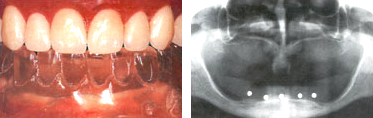

- 치료계획

구강검진, 치아모형 채득 및 방사선사진 촬영과 분석으로 몇 개의 임플란트를 어느 위치에 심을 것인지를 결정합니다.